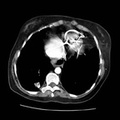

RADIOLOGY: LUNG: Case# 33689: PULMONARY NODULES. 32 year old woman. 1. Two pulmonary arteriovenous malformations consistent with the nodules seen on the recent chest film. There is breathing artifact on several of the images and other tiny AVMs cannot be excluded. 2. Cardiomegaly with right atrial and left atrial enlargement and hepatic congestion.